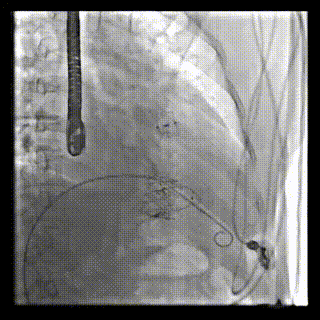

2021年12月24日,復(fù)旦大學(xué)附屬中山醫(yī)院葛均波院士團(tuán)隊(duì)成功應(yīng)用LuX-Valve Plus為一例極重度三尖瓣反流(TR)合并房顫、房缺的患者完成了經(jīng)血管三尖瓣置換術(shù),這是在前基礎(chǔ)上,本周完成的第三例經(jīng)血管三尖瓣置換手術(shù),葛均波院士、周達(dá)新教授等與心外科魏來教授、賴顥教授,心超室的潘翠珍教授、李偉教授及麻醉科的郭克芳教授共同完成了本周手術(shù),均獲得圓滿成功!患者術(shù)后超聲顯示無TR,臨床癥狀明顯改善。本周手術(shù)的成功也為L(zhǎng)uX-Valve Plus救治性臨床研究添上了濃墨重彩的一筆。

本周三例接受LuX-Valve Plus經(jīng)血管三尖瓣置換術(shù)的患者中,第一例患者為冠狀動(dòng)脈旁路移植術(shù)+Bentall+二尖瓣成形術(shù)后;第二例患者為永久起搏器植入術(shù)后,存在跨三尖瓣導(dǎo)線;第三例患者合并房顫、房缺及左心耳封堵術(shù)后。

三例患者入院后,葛均波院士團(tuán)隊(duì)周達(dá)新教授、潘文志教授、張?jiān)床┦?、陳莎莎博士及心超室的潘翠珍教授、李偉教授?duì)患者的情況進(jìn)行詳細(xì)評(píng)估和討論,最終決定為三例患者選擇LuX-Valve Plus40mm、50mm和50mm型號(hào)的瓣膜進(jìn)行手術(shù)治療。手術(shù)后即刻拔除氣管插管,術(shù)后患者三尖瓣反流癥狀得到顯著改善,復(fù)查心超結(jié)果顯示人工三尖瓣瓣膜支架固定穩(wěn)定,瓣葉關(guān)閉形態(tài)未見異常,未見明顯反流。